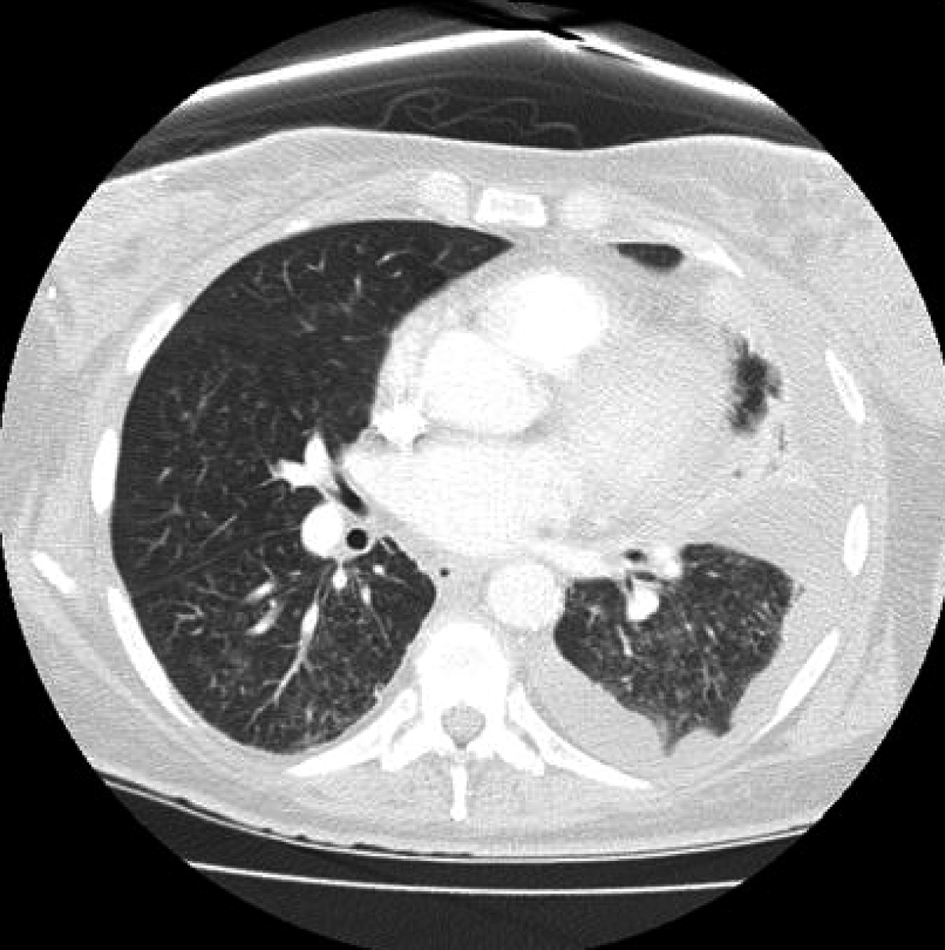

On day 16 after consolidation, sudden onset of dyspnea (PO2 60 mmHg, oxygen saturation 80%, PCO2 57 mmHg) and fever (38.3 degrees Celsius) developed. Blood pressure was 125/68, heart rate 80 beats/minute, and respirations 18/minute. No recent blood transfusions had been given for 3 days. Chest CT showed diffuse interstitial infiltrates and a new left sided pleural effusion suggestive of atypical pneumonia (Fig. 1). CT abdomen showed no hepatosplenic lesions. Cefepime, linezolid were continued and azithromycin added. After intensive care unit (ICU) transfer, non-invasive positive pressure ventilation (BIPAP) was begun. Echocardiogram showed left ventricular ejection fraction 55-60%. Bronchoscopy and bronchoalveolar lavage (BAL) showed no growth on bacterial, fungal or mycobacterial cultures. Serum cytomegalovirus deoxyribonucleic acid polymerase chain reaction (CMV DNA PCR) and adenovirus DNA PCR were negative. BAL was negative for respiratory viruses by PCR (influenza A and B, respiratory syncytial virus, parainfluenza virus, human metapneumonovirus, rhinovirus, and adenovirus). Transbronchial biopsy was not done due to thrombocytopenia. Aerobic, anaerobic, fungal and mycobacterial blood and sputum cultures were negative. Diagnostic thoracentesis of a 100 mL was transudative with negative bacterial, fungal and mycobacterial cultures. Gomori methenamine silver stain, acid fast bacilli stain and Fite stain were negative on the BAL and pleural fluid and there was no evidence of Pneumocystis jirovecii or nocardiosis. Furosemide had no response. Given the negative infectious workup and the correlation of her acute respiratory symptoms with neutrophil recovery, methylprednisolone 2 mg/kg/ day was given for immune reconstitution inflammatory syndrome (IRIS). She improved dramatically in 24 hours. BIPAP was discontinued. She was discharged from the ICU the next day and went home 4 days later on a tapering course of prednisone without the need for supplemental oxygen. Chest CT showed good resolution of the pleural effusion and interstitial infiltrates (Fig. 2). Prompt identification of IRIS and initiation of corticosteroids led to avoidance of mechanical ventilation and possibly a prolonged ICU course.

![]() Click for large image | Figure 1. Sudden onset of diffuse interstitial infiltrates and left sided pleural effusion. |